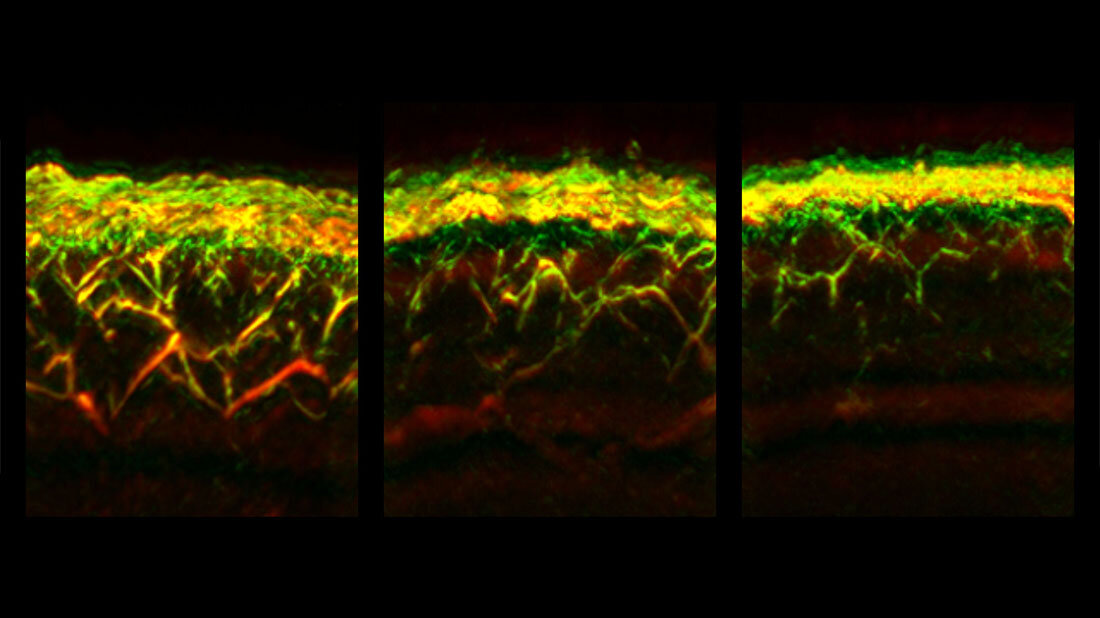

Verschiedene Auswirkungen auf unterschiedliche Hautschichten

Bei einer einzelnen RSOM-Messung können gleichzeitig Daten zu verschiedenen Tiefen der Haut gewonnen werden. Dadurch konnten die Forscherinnen und Forscher erstmals feststellen, dass sich Diabetes unterschiedlich auf Gefäße in verschiedenen Hautschichten auswirkt: Während beispielsweise die Zahl der Gefäße und Verästelungen in der sogenannten dermalen Ebene verringert waren, waren sie dichter unter der Hautoberfläche, in der sogenannten epidermalen Ebene, erhöht.